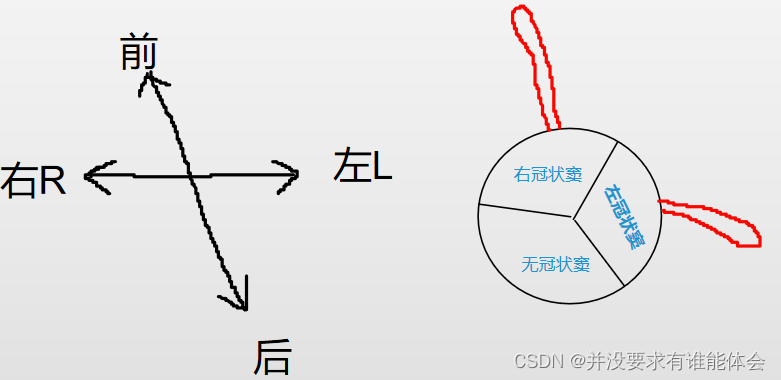

冠脉解剖-起源

冠状动脉通常起源于主动脉冠状动脉窦,右冠状动脉起源于右冠状窦(位于前方),左冠状动脉干起源于左冠状窦(左后方)

无冠状窦:(右后方)